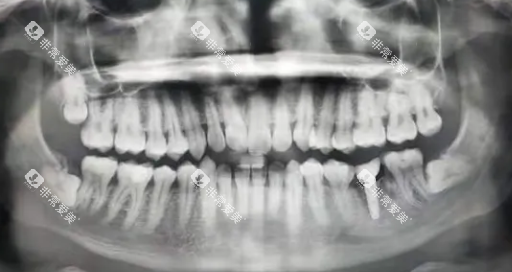

术前影像检查:必要的基础收费

拔智齿前需通过影像检查明确智齿位置、牙根形态及与周围组织的关系,这项检查为必做项目,收费独立于拔牙费用之外。

口腔全景片:80-150元起

可清晰显示全口牙齿及牙槽骨整体情况,适用于大多数正位或简单阻生智齿,是钦州本地拔智齿比较常用的影像检查方式,检查时间约5分钟。

锥形束CT(CBCT):200-350元起

提供三维立体影像,能正确定位埋伏智齿与神经的距离,适用于复杂阻生或埋伏智齿,这类检查在钦州本地的使用率约为30%,主要针对高难度病例。